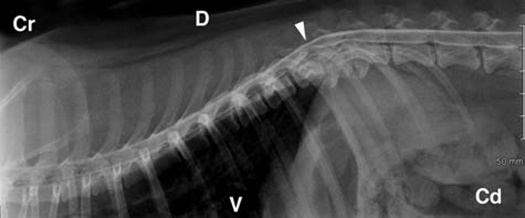

Πλάγια προβολή. Η μυελογραφία στο Pug έδειξε συμπίεση μεταξύ Θ11-Θ12